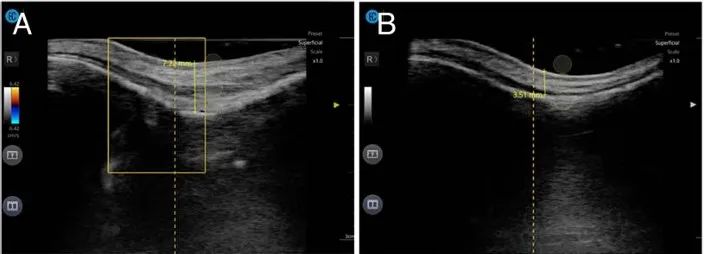

图3:鼻背的超声评估。(A) 治疗前,骨与皮肤的距离测量为7.22mm,低回声层表明残留透明质酸。(B) 一周后,低回声区明显缩小,骨与皮肤的距离缩短至3.51mm。